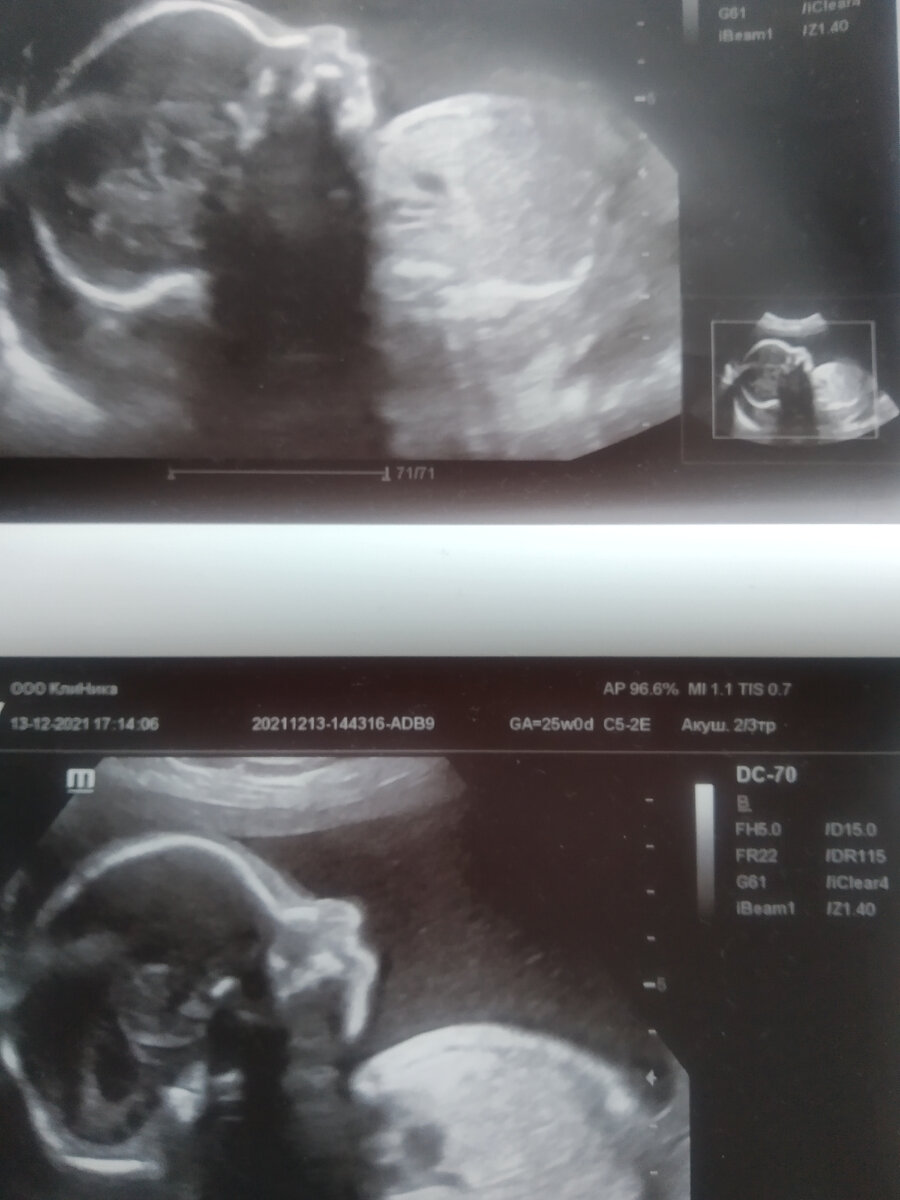

1 скрининг и УЗИ сделала бесплатно. Очень не понравилось. Толком ничего не рассмотрели, в описании прочерки просто поставили. Не нашли нос..Да и ладно, в следующий раз посмотрим.. Отсутсвие носа меня тогда конкретно напугало. Оказалось потом, что это отсутсвие зрения у узиста. Переделала платно УЗИ за 2 000- прекрасный носик мне даже показали. И мужа пригласили посмотреть.

Последующие делала платно. Второй и третий скрининг по 2 500.

С 25 недели начались проблемы с течением беременности. Назначили гормоны и кучу витаминов. Также рекомендовали УЗИ контроль раз в 10 дней и КТГ еженедельно. Итого : гормоны с 25 по 36 неделю - 7000. Витамины (поливитамины, железо, магний) 15 000. Бесплатно выдали упаковку йодомарина. УЗИ 7 раз помимо скрининга по 1200 - 8 400Ктг бесплатно.